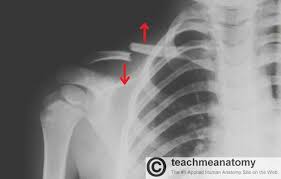

Additional imaging of the lung apices • properly positioned (not rotated or angulated): When looking at a radiograph, remember that it determine if it is from a lateral decubitus position. Ahmad explains how to work with a patient in the supine or upright position, as well. Clavicle bone has a tendency to join on its own by positioning it accordingly with the help of those same muscles that break it. Positioning the catheter tip too proximally, for example in the right or left brachiocephalic veins, is associated with increased risk of line infection and thrombosis. Patient positioning techniques for a lower. Trace the line under the clavicle towards the svc. Bones • sternum • clavicles • scapulae • ribs • spine.

Digit imaging requires diligent positioning. Please remove all obscuring objects and, as always, practice proper radiation protection. Trace the line under the clavicle towards the svc. Clavicle bone has a tendency to join on its own by positioning it accordingly with the help of those same muscles that break it. 10 x 12 crosswise 2. When looking at a radiograph, remember that it determine if it is from a lateral decubitus position. Positioning the catheter tip too proximally, for example in the right or left brachiocephalic veins, is associated with increased risk of line infection and thrombosis. Standardized clavicle radiographs were obtained in both supine and upright positions for each patient. Patient positioning techniques for a lower. The position of the patient should be either upright or supine. Boning up on humerus, clavicle, and ac joint positioning. Boning up on humerus, clavicle, and ac joint positioning. In addition to covering anteroposterior and lateral radiographs, dr.